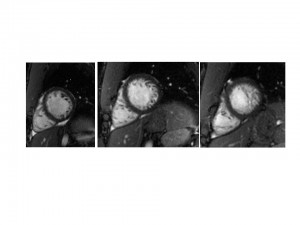

An MRI was performed to confirm the diagnosis.

A detailed review showed mild biventricular enlargement with a ratio of thick, noncompacted to thin, compacted myocardium of 2.0. (The best distinguishing feature for LV noncompaction was a maximum ratio in diastole of noncompacted-to-compacted myocardial thickness of >2.3 to 1, as assessed in three long-axis views.)